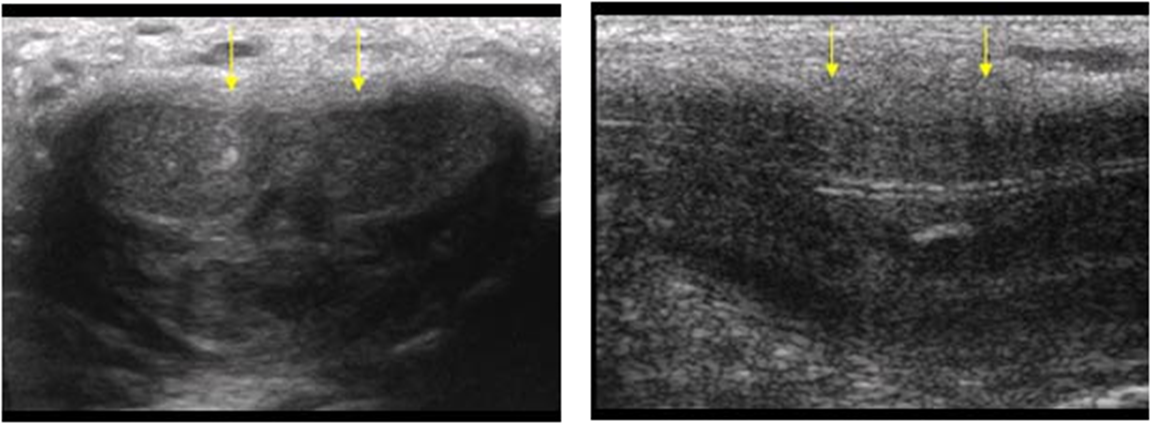

What are these images showing?

peyronies